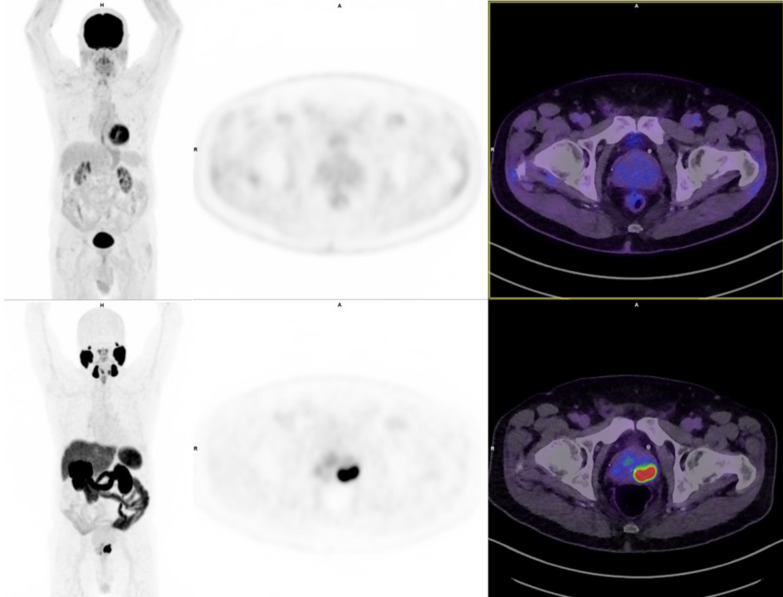

Background: Despite being a potentially attractive alternative molecular imaging modality due to wider availability and association with lethal disease in advanced prostate cancer, the role of fluorodeoxyglucose (FDG)- positron emission tomography (PET) at initial diagnosis compared to Prostate Specific Membrane Antigen (PSMA) PET is yet to be accurately determined. The aim of this study was to evaluate the additive benefit of FDG PET to PSMA PET in patients with newly diagnosed, high risk prostate cancer.

Results: A prospective trial conducted across three sites between October-2021 and January-2023 recruited 32 participants with high risk (EAU classification) prostate cancer staged with PSMA PET-CT. FDG PET-CT was acquired centrally and reported with a standardised template. Median age was 69 years, median PSA was 14 ug/L, and most had PI-RADS 5 scores (59%) and ISUP Grade Group 5 tumours (66%). Overall, FDG-PET did not detect any additional definite/probable metastasis according to physician interpretation. All tumours showed PSMA avidity and higher stage was observed per PSMA-PET in 5 participants. No FDG uptake at the primary tumour occurred in 34% of participants. FDG-PET did not result in a change in management for any participant. PSA remission rates were lower in patients with stage ≥ 3 tumours on MRI (60% vs 94%, p = 0.04). Patient reported outcomes (PROs) were largely stable throughout the study.

Conclusions: FDG-PET did not provide additive staging information above PSMA-PET or alter management for newly diagnosed high-risk prostate cancer patients.